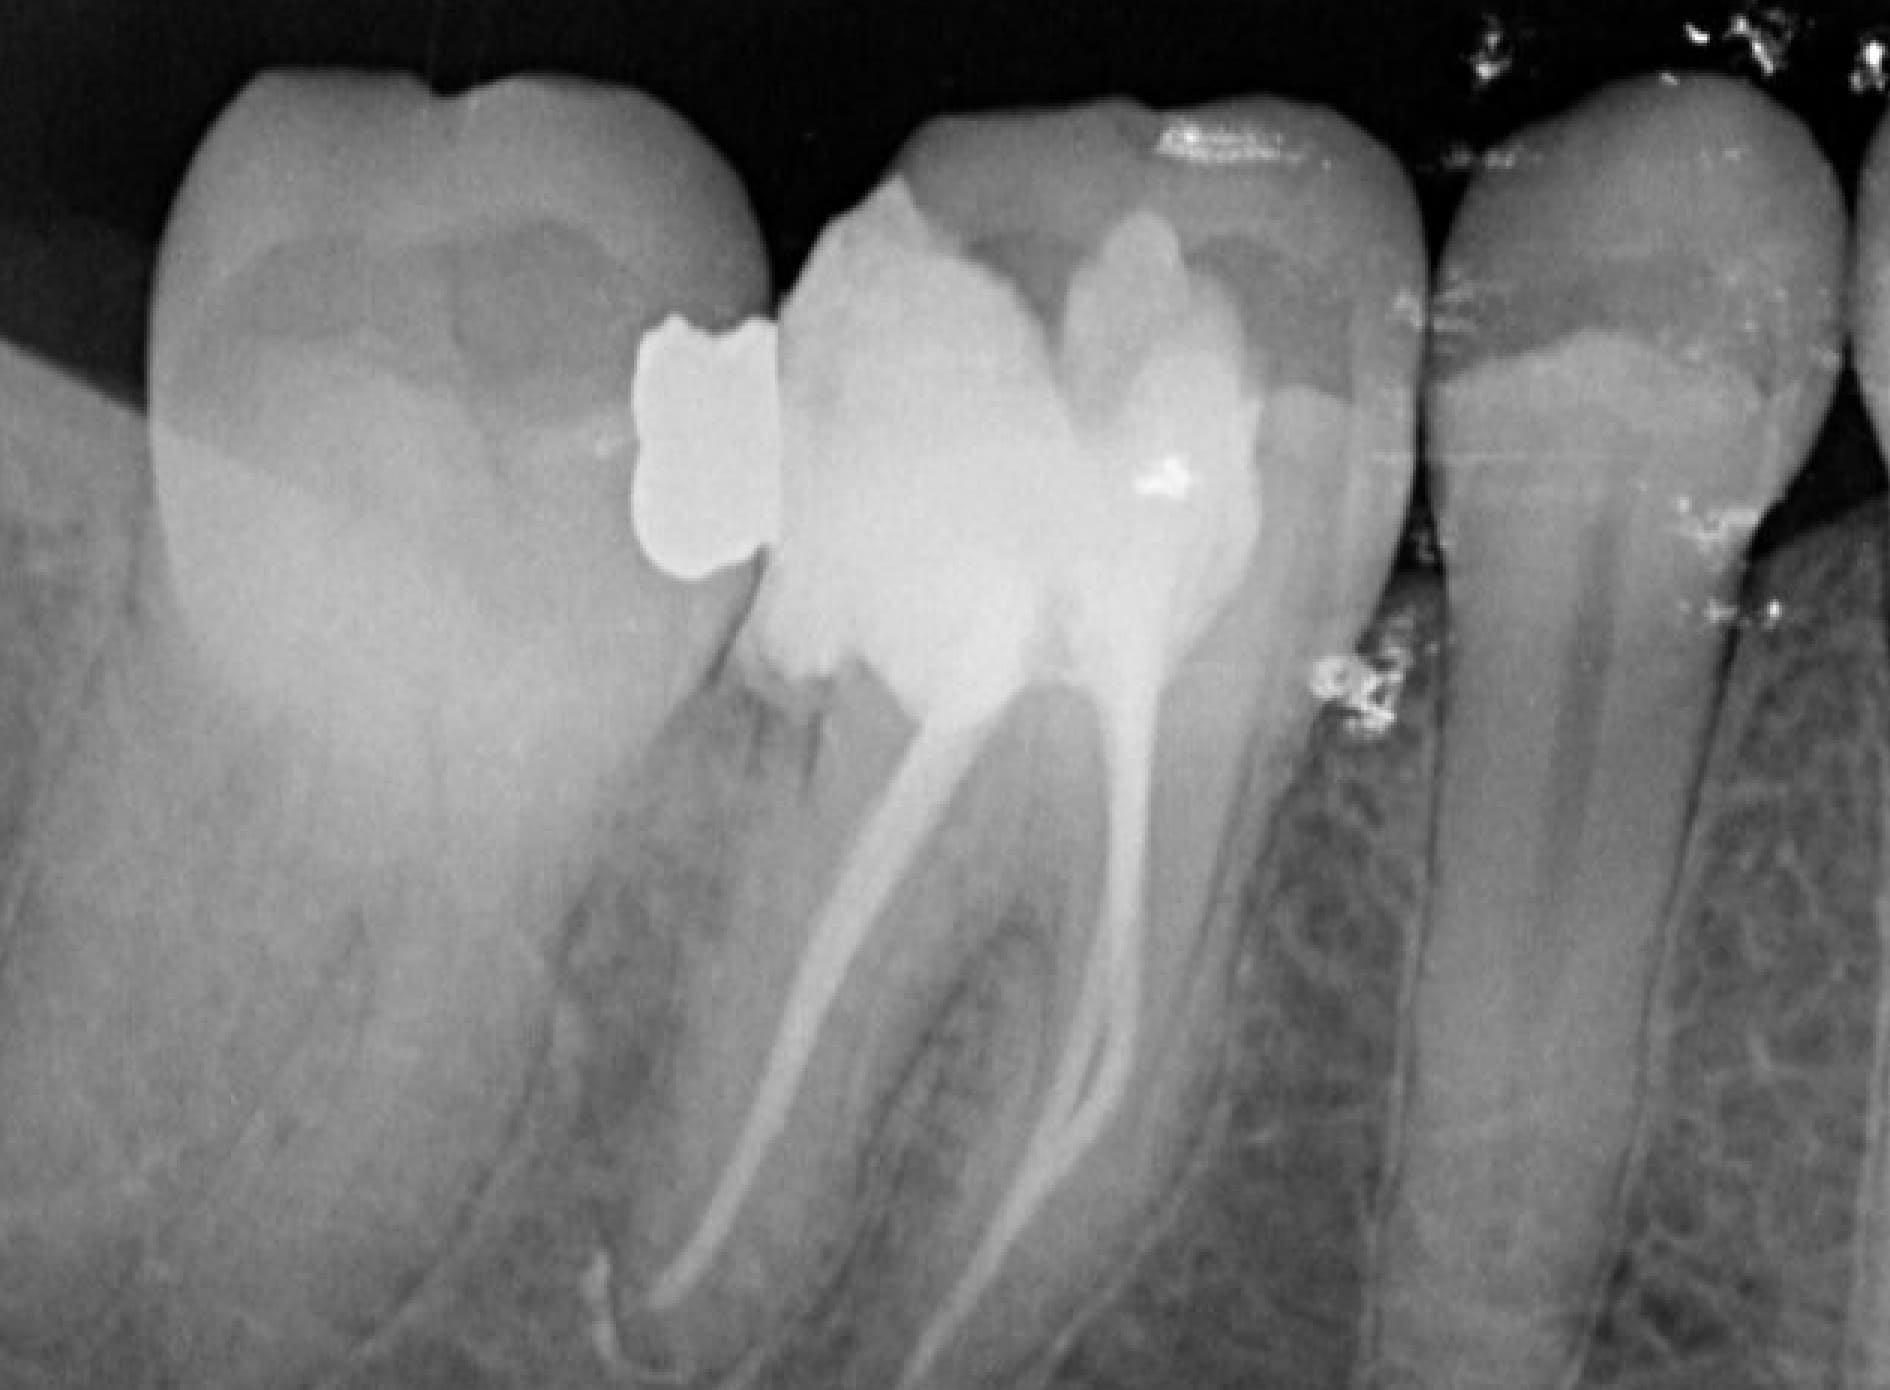

Una endodoncia es un procedimiento de alta precisión para salvar un diente que de otra manera tendría que ser extraído. En GM Dent, usamos tecnología moderna para garantizar un proceso cómodo y seguro.

Tratamiento de Endodoncia